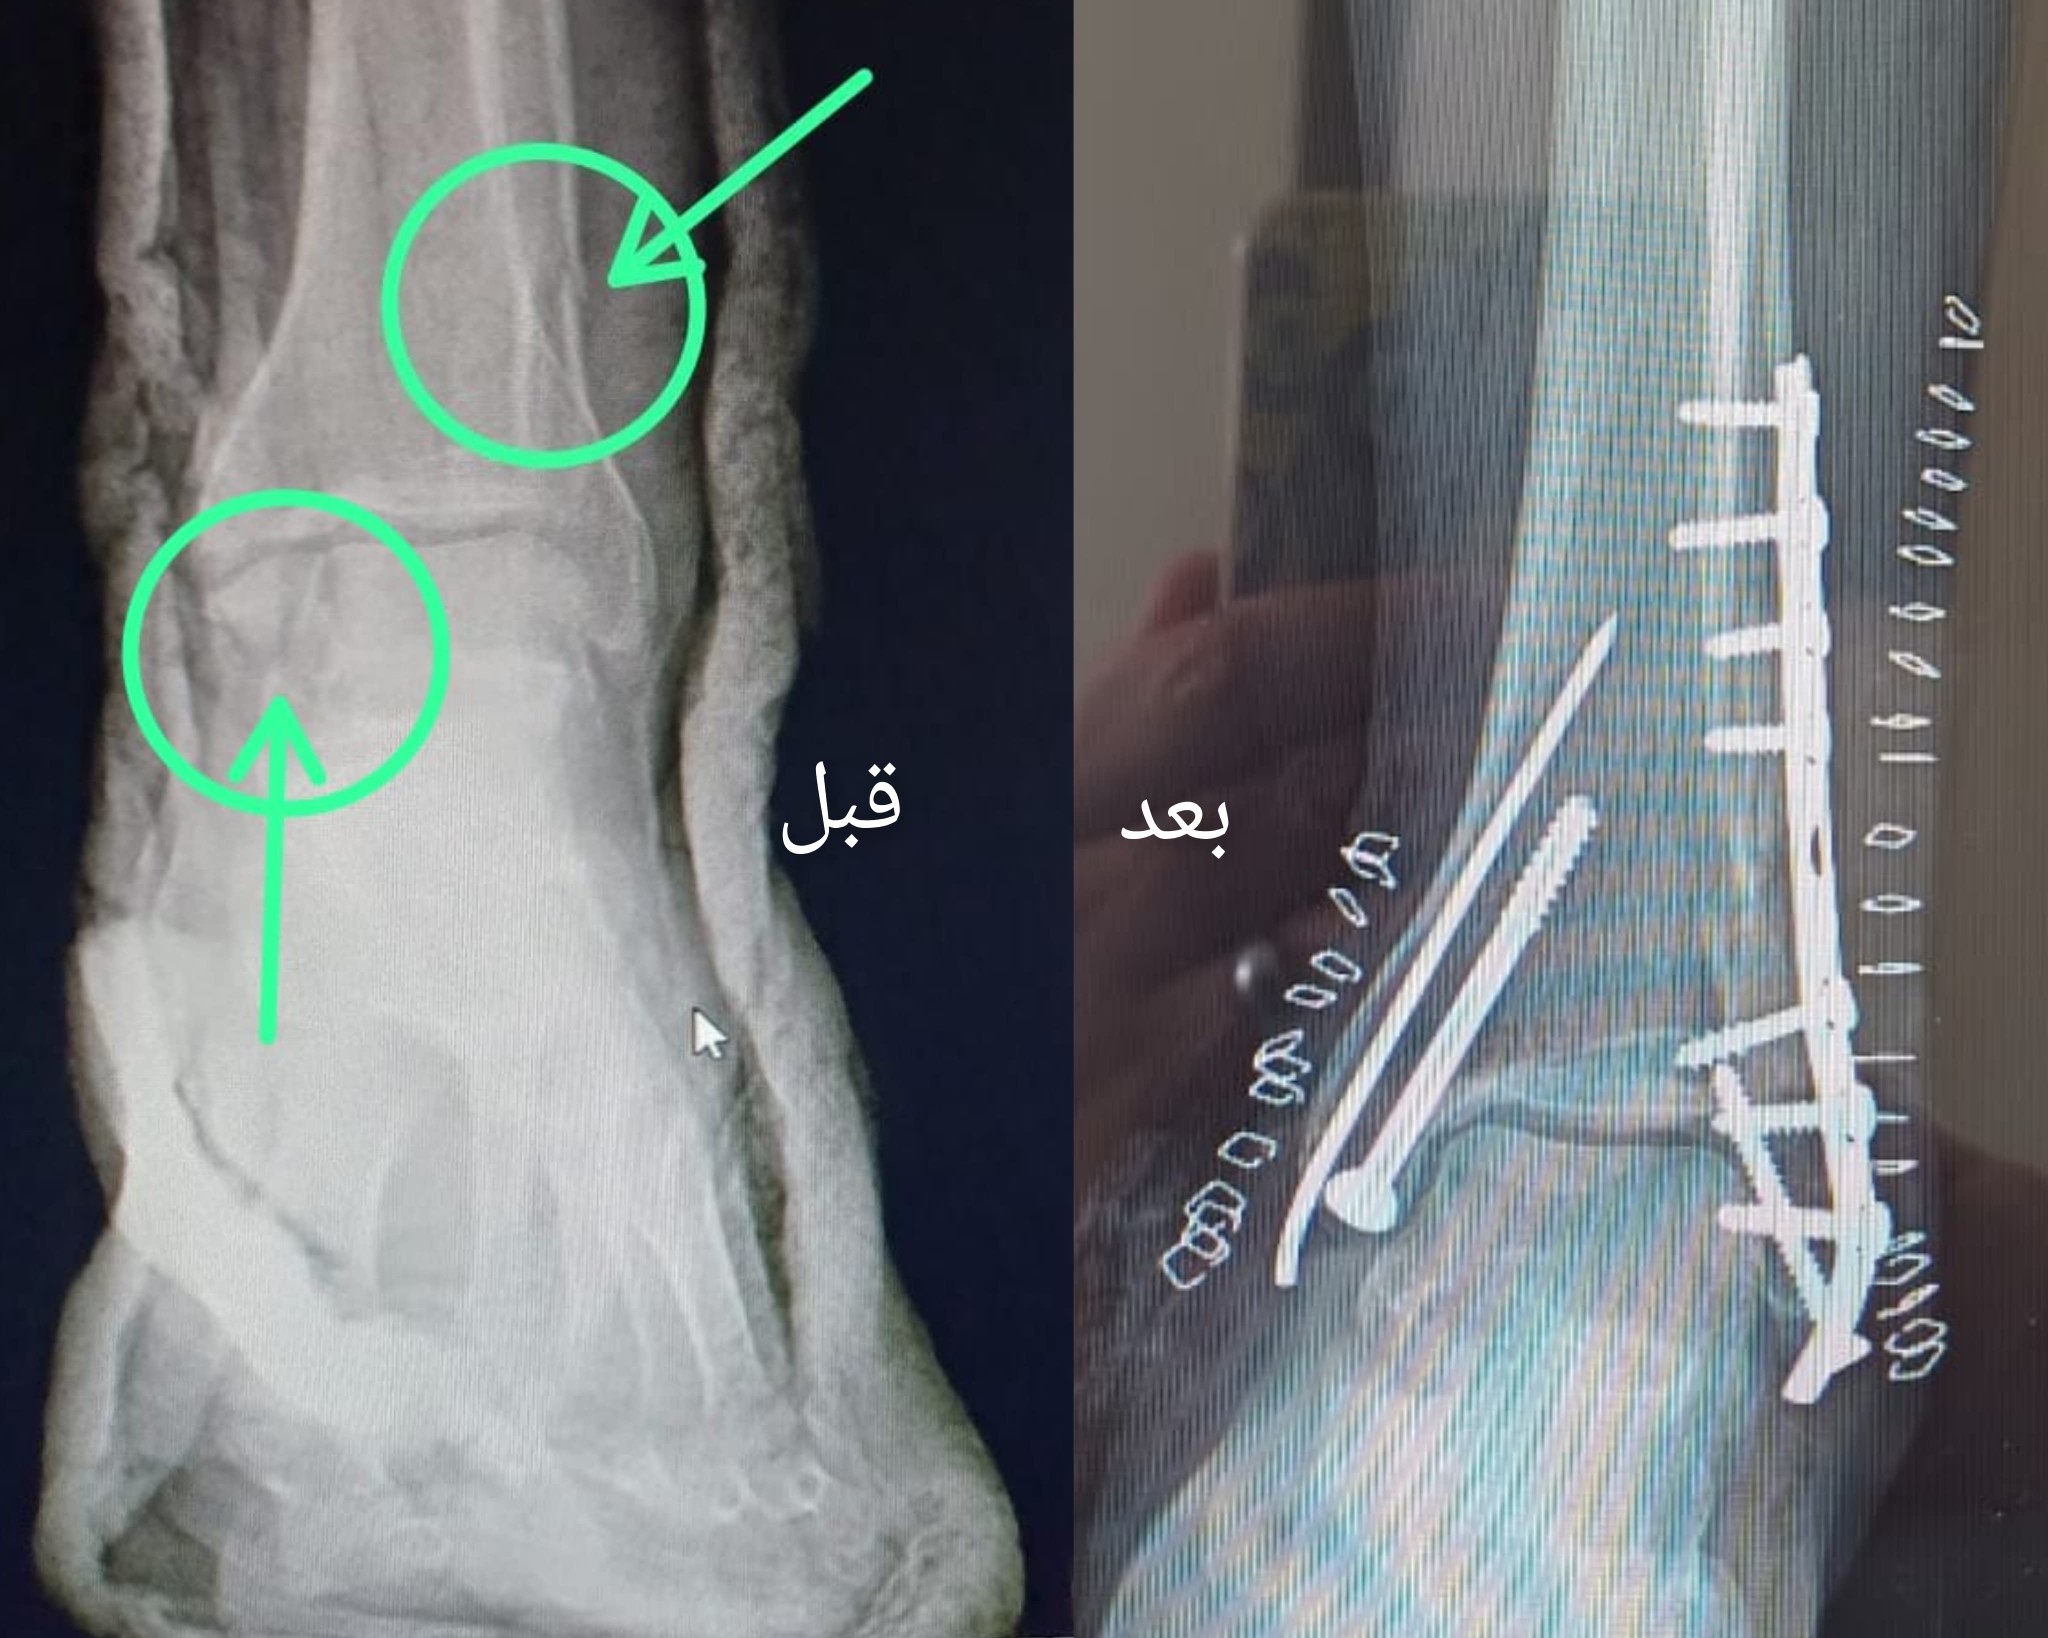

أعلنت مستشفى الشيخ زويد المركزي تحقيق قسم جراحة العظام إنجازًا جديدًا، حيث حضر مريض إلي قسم الاستقبال يبلغ من العمر ٣٠ عامًا، الخميس الماضي، يعاني من كسور مفتتة ومتعددة بعظام الساق اليسري ومفصل الكاحل الأيسر ما بعد إدعاء حادث وهي من الكسور الحرجة التي تهدد القدرة على الحركة وتؤدي إلى مضاعفات خطيرة.

وتم على الفور عمل الإسعافات الأولية بقسم الأستقبال وتحضير المريض للعمليات، وتم العلاج بتصليح الكسور جراحياً وتثبيتها بشرائح ومسامير لرد وتثبيت الكسر والحفاظ على عظام الساق ومساعدة المريض على استعادة قدرته على الحركة بشكل طبيعي باستخدام أحدث التقنيات في تثبيت الكسور.